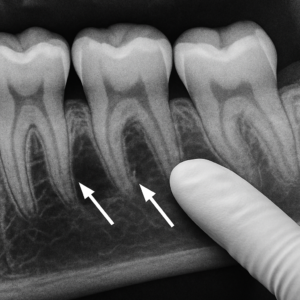

The process of getting dental implants involves a few stages, usually spread over a couple of months. It begins with a consultation with an oral surgeon who assesses your eligibility for the procedure. The implant, a small titanium post, is then placed into the bone socket of the missing tooth. As the jawbone heals, it grows around the implant, securing it. Once healed, a small connector post, or abutment, is attached to the implant to hold the new tooth.